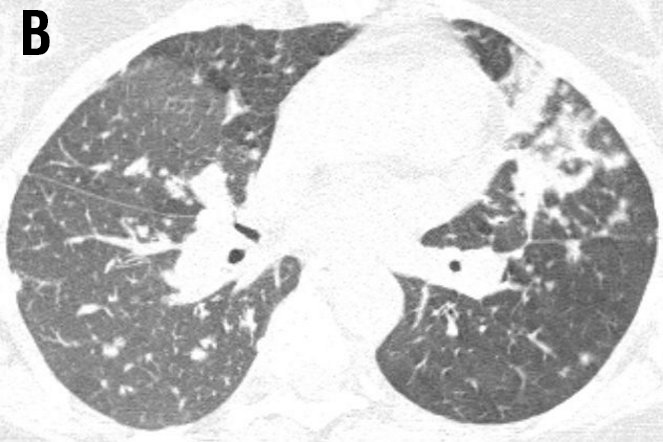

A 40-year-old female was referred to the ild care centre of the MUMC (a tertiary referral centre for sarcoidosis in the Netherlands) with refractory sarcoidosis. She was suffering from severe fatigue, shortness of breath on exertion, coughing, arthralgia and skin lesions, and also described exercise intolerance. She had no other medical history of note. An open lung biopsy showed non-caseating granulomatous inflammation consistent with the diagnosis sarcoidosis. Initially, she was treated with prednisone starting with 40mg daily. As this did not reveal a clinical improvement methotrexate was added (12.5mg once a week together with folic acid 5mg also once a week). However, this was without benefit, she deteriorated and responded neither to corticosteroids nor to methotrexate. At that time radiography and high resolution CT scan of the chest showed enlarged mediastinal en hilar lymph nodes and diffuse intrapulmonary lesions (figure 1 a and b).

Figure 1 Radiography and high resolution CT (HRCT) scan of the chest showed enlarged mediastinal and hilar lymph nodes (LN: 3) with intraparenchymal nodules (ND: 2), septal and non-septal lines (LS: 2) thickening and irregularity of the bronchovascular bundles (BVB: 1); parenchymal consolidations( PC: 3; including ground-glass opacifications) with focal pleural thickening (PL: 1), respectively (total visual Oberstein score (7,8) 13; Figure 1A).